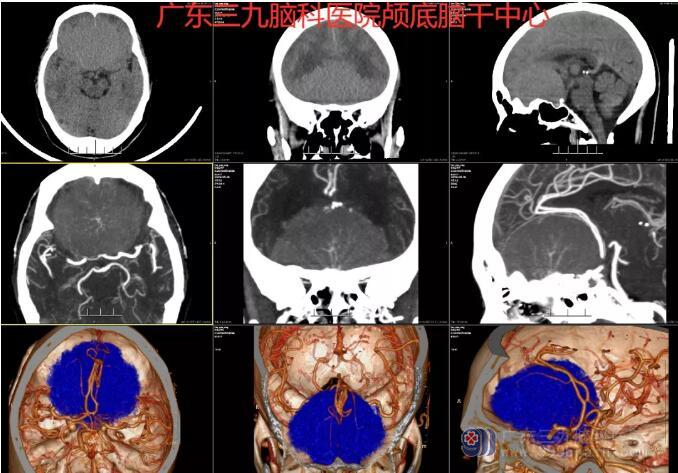

图1:术前CTA示前颅窝底示一巨大占位性病变,范围约6.8cm×3.9cm×5.7cm,其内示多发发自颅底的细小血管影,邻近双侧大脑前动脉A1、2段及颈内动脉末端受压后移;右侧大脑前动脉A1段细小;余双侧大脑中与后动脉走行略僵硬,左侧颈内动脉眼段内下缘示一小突起影,大小约3.4×2.6mm,左侧大脑中动脉M1段示一囊状小突起影,大小约3.6×3.2mm